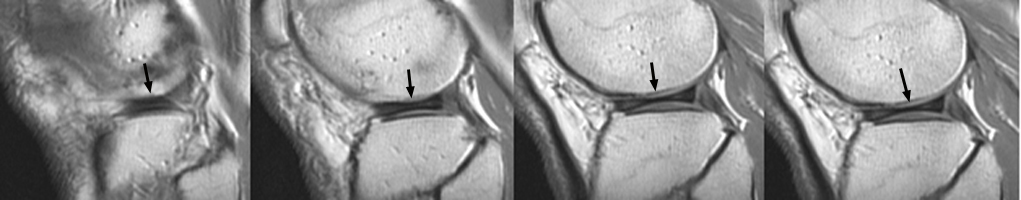

Seen on sagittal images, the bow-tie represents the continuity of the meniscus between the anterior and posterior horns. It is normally seen on 2 contiguous sagittal images. When it is seen on 3 or more contiguous 5 mm thick sagittal images is indicative of a discoid meniscus.

Discoid Meniscus - Click on the image for a larger version